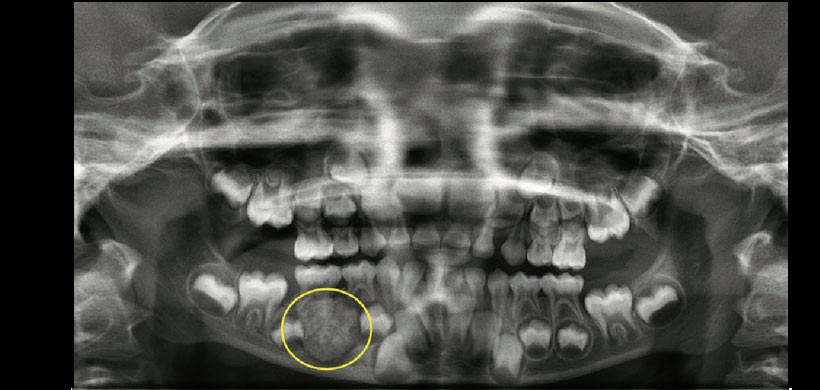

Figura 2: Radiografía panorámica preoperatoria, que muestra una imagen radiopaca de límites definidos rodeado de un halo radiolucido, asociada a la raíz mesial de la pieza 85, se visualiza el desplazamiento de los gérmenes dentarios de las piezas 44 y 45.r